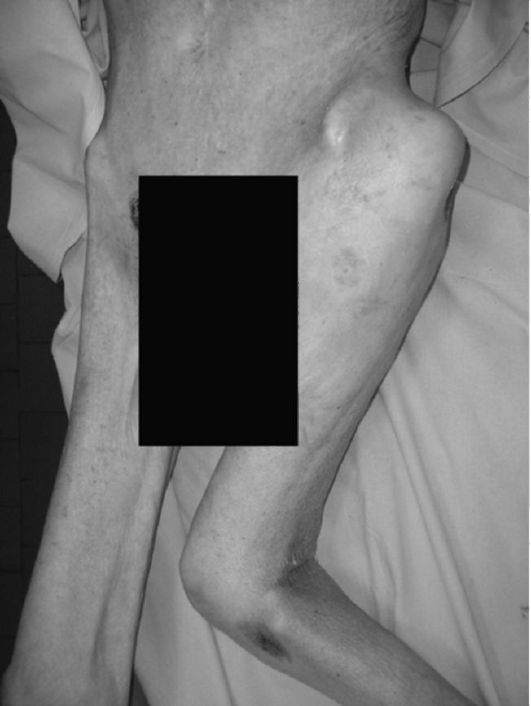

В восстановительной стадии полиомиелита имеет место обратное развитие параличей (обычно в сроки от 1 года до 2 лет). Стадия остаточных явлений, или резидуальный период полиомиелита, характеризуется разнообразием деформаций верхних, нижних конечностей и позвоночника в результате выпадения функции той или иной группы мышц. Парализованная конечность холодна на ощупь, несколько короче другой, мышцы атрофированы, эластичность сухожилий теряется, связочный аппарат растянут. Нарушение функции конечности связано с тяжестью поражения нервно-мышечного аппарата, в суставах развиваются контрактуры и деформации, кости конечностей истончены, в них выявляется остеопороз.

Паралитические деформации верхних конечностей встречаются крайне редко по сравнению с нижними конечностями. Страдают преимущественно мышцы верхнего плечевого пояса, из них чаще всего дельтовидная мышца, в результате чего больной не может поднять и отвести руку кнаружи и кзади.

При выпадении функции двуглавой мышцы плеча отсутствует активная функция сгибания в локтевом суставе; при выпадении функции трехглавой мышцы плеча нарушается активное разгибание в локтевом суставе. При параличе мышц предплечья и кисти возникают сгибательные контрактуры лучезапястного сустава и пальцев кисти.